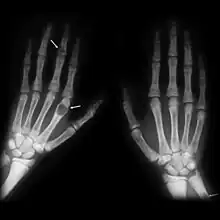

Generally, the first bones to be affected are the fingers, facial bones, ribs, and pelvis.[22][23] Long bones, which are longer than they are wide, are also among the first affected.[23] As the disease progresses, any bone may be affected.[18]

X-rays may also be used to diagnose the disease. Usually, these X-rays will show extremely thin bones, which are often bowed or fractured. However, such symptoms are also associated with other bone diseases, such as osteopenia or osteoporosis.[29] Generally, the first bones to show symptoms via X-ray are the fingers.[22] Furthermore, brown tumors, especially when manifested on facial bones, can be misdiagnosed as cancerous.[29] Radiographs distinctly show bone resorption and X-rays of the skull may depict an image often described as "ground glass" or "salt and pepper".[30][31] Dental X-rays may also be abnormal.[2]